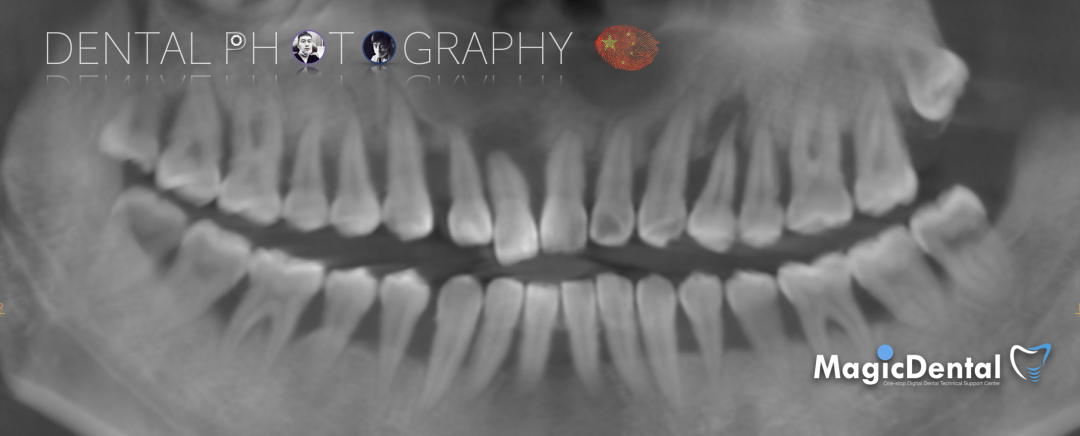

CT显示牙槽骨水平吸收严重,大多数吸收至根尖。

术前CBCT

CBCT显示全口牙槽骨水平吸收严重,下颌骨量保存大于上颌